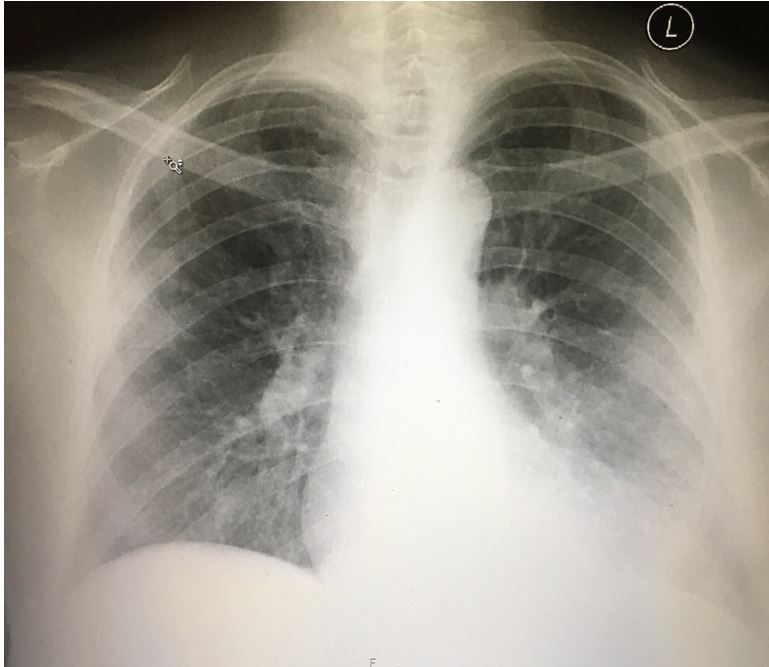

Patient's vital signs and results of physical examination are normal; results of a previous lumbar puncture also were normal. What does the chest x-ray reveal?

What does the case image show? The image shows bibasilar infiltrates that are worse on the left side.

What should you do next? Ask about exposure to livestock while in Australia and consider Q fever. Treat with appropriate antibiotics.